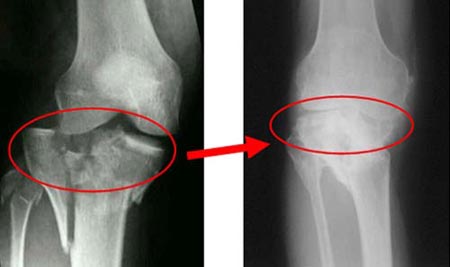

- На 1 степени остеофиты в при диагностике не обнаруживаются. Наблюдается некоторое сужение суставной щели.

- При поражении сустава 2 степени щель незначительно сужена, а остеофиты уже успели поразить поверхности кости. При остром артрозе наблюдается очень сильная боль.

- При поражении 3 степени щель заметно сужена, а на поверхности кости имеется большое количество остеофитов. При обострении повышается температура.

- 4 стадия артроза костей и суставов характеризуется тем, что суставной щели практически нет, а полость практически полностью поражена.